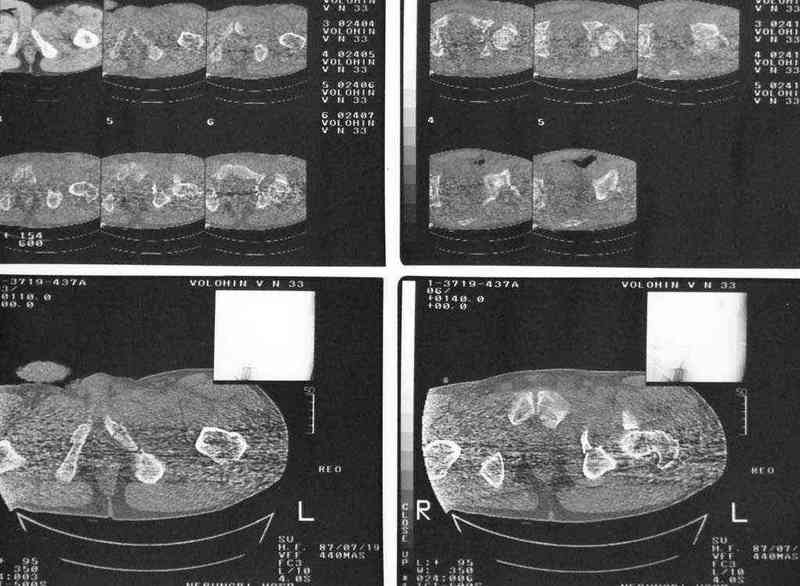

Дополнение, минимальный набор необходимых прекций, необходимых для лечения повреждений вертлужной впадины

Фас. Inlet

Подвздошная Запирательная

еще одно дополнение